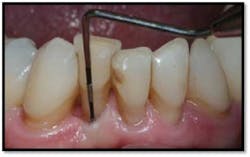

LL Quadrant#27M, now 2mm reduced from 6mm, tissue tight and firm

#26 DF, now 2mm from 8mm

#26 F now 2mm. All tissue is light pink, tight and firm.

Bone fill #26 and 27,no mobility